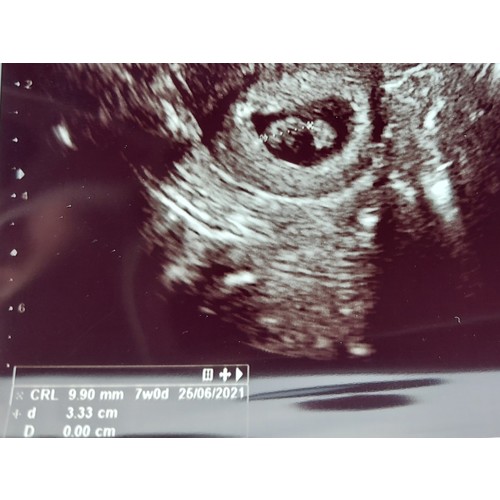

11 mm met 7 weken en 2 dagen!

9,90mm zie ik. Ben wel iets verder dan dat daar op staat. Ik ben vandaag 8+1 en deze echo was op 7+3 gemaakt.